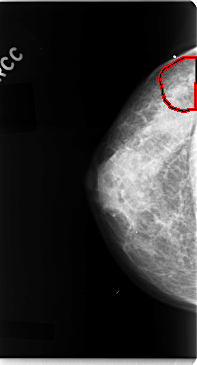

C_0077_1.RIGHT_CC

LEFT_CC LINES 4736 PIXELS_PER_LINE 2536 BITS_PER_PIXEL 12 RESOLUTION 50 NON_OVERLAY

FILE: C_0077_1.RIGHT_CC.OVERLAY

TOTAL_ABNORMALITIES 1

ABNORMALITY 1

LESION_TYPE MASS SHAPE IRREGULAR MARGINS ILL_DEFINED

ASSESSMENT 4

SUBTLETY 3

PATHOLOGY MALIGNANT

TOTAL_OUTLINES 1

BOUNDARY